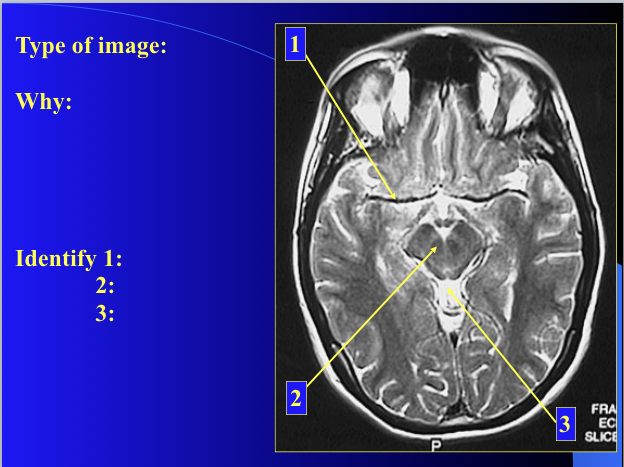

identify how the things look in the image

1) anterior commissure

2) interthalamic adhesion

3) third ventricle

4) spleneium

5) cingulate gyrus